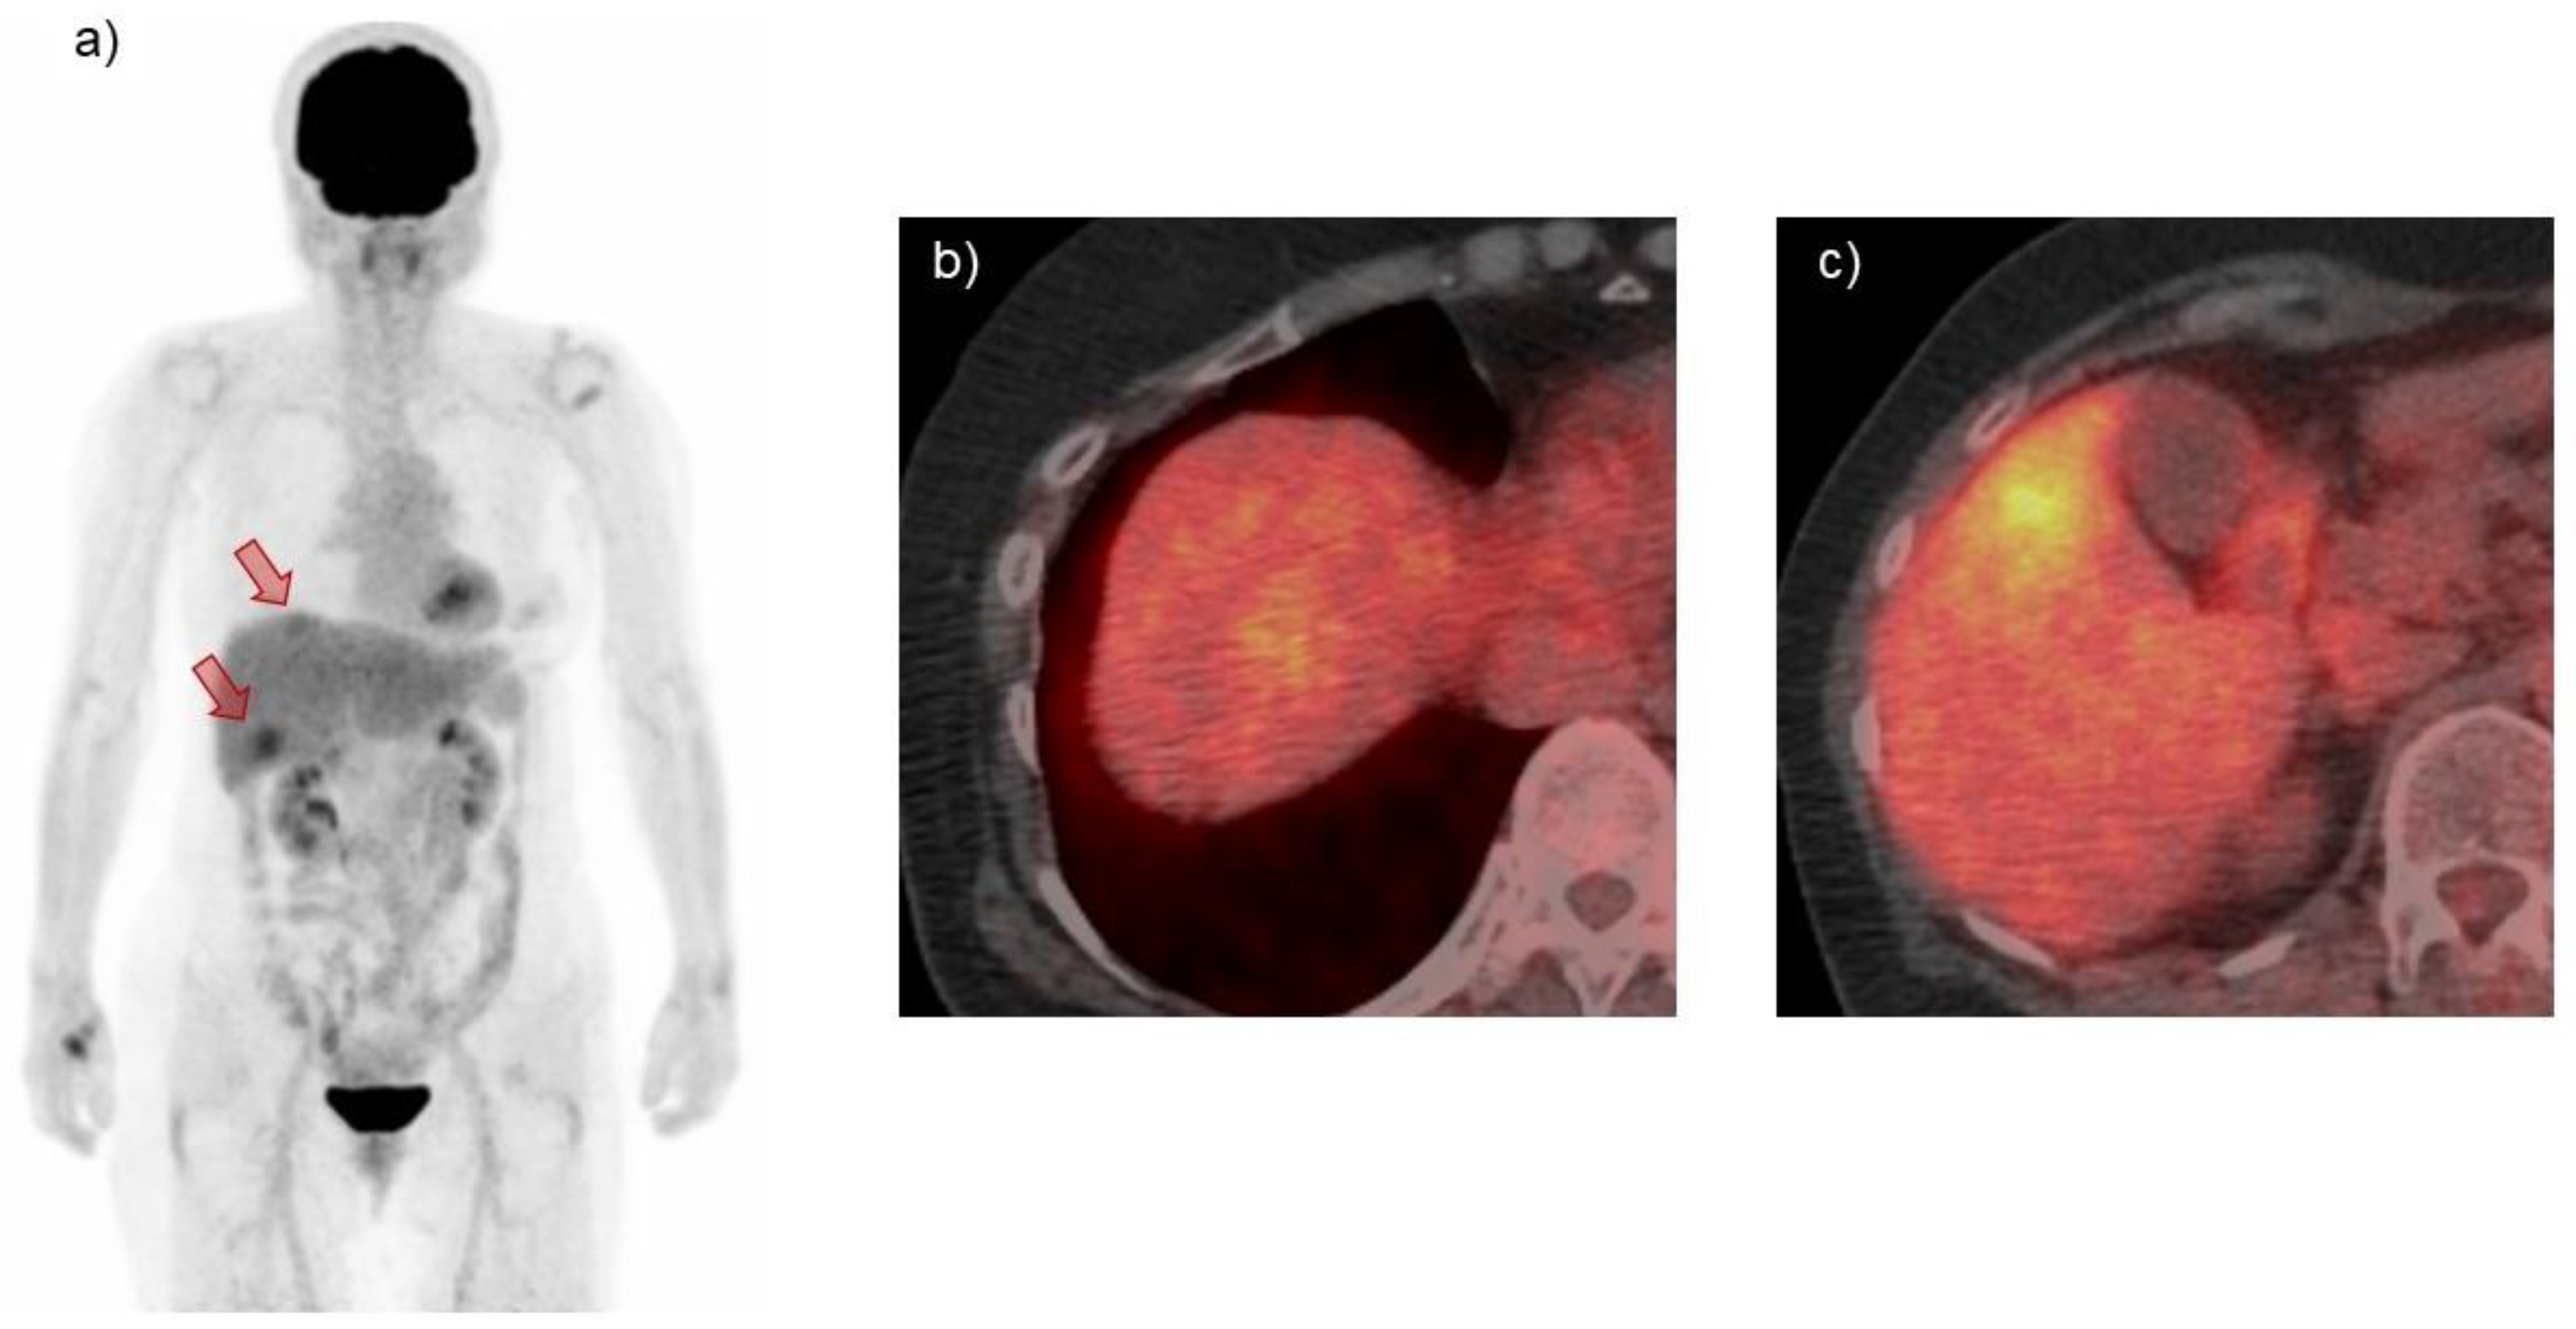

| PET | Abnormal accumulation | Abnormal accumulation | Nearly half of cases have no accumulation |